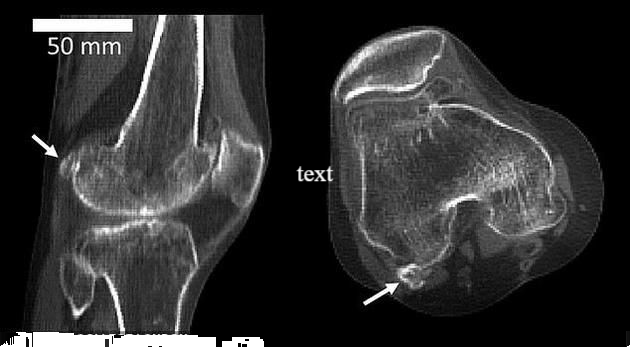

其实这个东西叫做法贝骨 , 这是一种人体内极为罕见的骨头 , 世界上只有少数人体内拥有这种骨头 。 因为人类在进化的过程中 , 早已经将其给进化掉了 。

据了解 , 这骨头位于膝盖处 , 一般在哺乳动物的身上比较常见 , 尤其是一些灵长类的动物 , 比如说像猩猩和猴子 。 但是人类的身上 , 现在基本上是看不到的 , 因为用进废退的道理 , 相信大家都懂 。

根据数据显示 , 其实最早发现法贝骨是在1875年 。 当时拥有法贝骨的人的数量已经占据了人类总数量的百分之11 , 在2018年已经到达了40% 。 我们从数据来分析 , 其实这个法贝骨拥有的人数 , 其实在逐年上升的 。

至于为什么会重新出现 , 其实根据科学家的说法 , 这个是与人类的活动有关的 。 而这块骨头的出现 , 可以增强膝关节的能力抵御身体给膝盖带来的压力 , 避免膝盖之间的摩擦和劳损 。 也就是说 , 可能是因为人类的运动量增加 , 所以这块骨头重新出现 。 另外一种说法 , 就是人类的生活水平提高 , 物质水平的提高 , 导致这块骨头的出现 , 至于是退化还是进化 , 现在科学界还存在于一定的争议 。